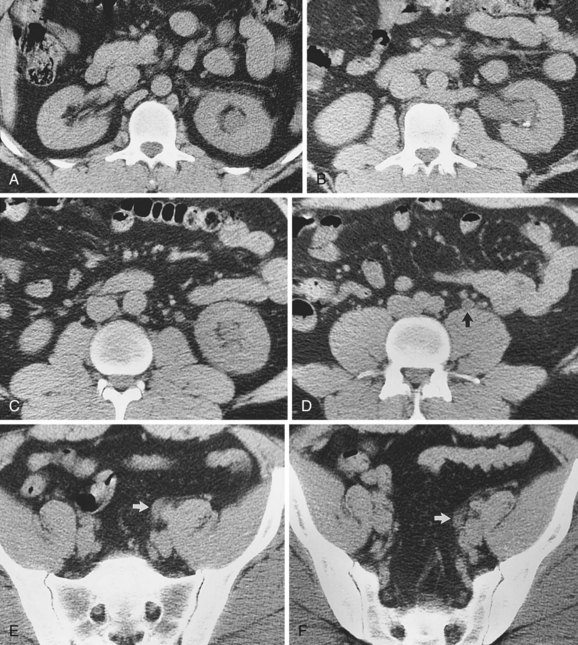

Doppler ultrasound may be helpful in evaluating the renal artery and renal vein and assessing the vascular resistance in the kidney. Doppler modes may also be useful in evaluating neovascularity associated with renal tumors and in correctly characterizing hypoechoic structures in the renal pelvis such as a parapelvic cyst, the renal vein, or the dilated collecting system.

Some patients are not favorable candidates for renal ultrasonography. Obesity, intestinal gas, and physical deformity may be impediments to complete renal evaluation. Renal ultrasonography has poor sensitivity for renal masses less than 2 cm (Warshauer et al, 1988). There is a lack of specificity for renal tumor type except for angiomyolipoma. Angiomyolipoma has characteristics that are distinctive on ultrasonography (highly echoic), but some small renal cell carcinomas have been shown to be indistinguishable from angiomyolipoma by ultrasound criteria (Yamashita et al, 1992; Forman et al, 1993).

Transabdominal pelvic ultrasonography is a tremendously versatile tool for the urologist. It is a noninvasive method for evaluating the lower urinary tract and prostate in men and the bladder in women. A curved array transducer of 3.5 to 5 MHz is most commonly employed to perform transabdominal ultrasonography. In pediatric patients a higher-frequency transducer may be used. In cases where only a residual urine or bladder volume is to be determined, an automated bladder scanner is often employed.

Bladder ultrasonography is most commonly performed with the patient supine and the sonographer on the patient’s right side. The scan should be performed in a warm room, and the patient draped to provide for comfort and privacy. If necessary, a roll may be placed beneath the patient’s hips. Scanning technique depends on the circumstances and the reason for the examination but in general should be performed with a moderately filled bladder. The bladder should be scanned in a sagittal and transverse manner angling the probe into the pelvis so that the bladder can be visualized beneath the pubic bone. Although the prostate cannot be imaged with the same resolution achieved during transrectal scanning, the size and morphology of the prostate can be demonstrated. Although transabdominal scanning is the most common means of evaluating the bladder, the bladder may also be assessed via a transvaginal and transrectal approach. These approaches are useful in patients who are obese or who are not suitable candidates for transabdominal scanning.

Transabdominal pelvic ultrasonography should include evaluation of the lumen of the bladder, as well as bladder wall configuration and thickness. The presence of specific lesions such as stones or tumors should be documented. The structures immediately surrounding the bladder may also be evaluated including the distal ureters, the prostate in men, and the uterus and ovaries in women (Fig. 4–34). The emergence of urine from the ureteral orifices (ureteral jets) can be demonstrated. The clinical value of demonstrating ureteral jets has been questioned. Up to 10 minutes of continuous observation may be required to verify the absence of a ureteral jet (Fig. 4–35) (Delair and Kurzrock, 2006).

Figure 4–34 A, Transverse view of the bladder in this female patient demonstrates the uterus (U). B, Sagittal view of the bladder shows the uterus posterior to the bladder.

Figure 4–35 In this transverse view of the bladder, urine “jets” emerging from the left (arrow) and right (arrowhead) ureteral orifices are demonstrated by power Doppler.

Bladder volume can be calculated manually by obtaining measurements in the midtransverse and midsagittal planes (Fig. 4–36). Numerous studies have shown that for bladder volumes between 100 and 500 mL, such calculated volumes are within 10% to 20% of the actual bladder volume (Roehrborn et al, 1986).

Figure 4–36 Measurement of bladder volume using this formula: bladder volume = width (transverse plane) × height (transverse plane) × length (midsagittal plane) × 0.625. In the sagittal plane, the dome (D) of the bladder is to the left and the prostate (P) to the right.

Measuring bladder wall thickness may assist the clinician in understanding the degree of bladder outlet obstruction (Fig. 4–37). Bladder wall thickness varies depending on the volume of urine in the bladder and on which part of the bladder wall is measured. It has been shown that measuring bladder wall thickness may predict bladder outlet obstruction with greater accuracy than free uroflowmetry, postvoid residual urine, and prostate volume (Oelke et al, 2007).

Figure 4–37 Bladder wall thickness may provide information about bladder outlet obstruction. In this sagittal view, bladder wall thickness is measured posteriorly (arrow) near the midline. Note the trabeculation of the relatively hyperechoic bladder wall.

Transabdominal prostatic ultrasonography requires angling the probe beneath the pubic bone. In the transverse plane the transducer is fanned inferiorly until the largest transverse diameter of the prostate is identified. Measurements of the transverse width and height are obtained (Fig. 4–38A). The transducer is then rotated 90 degrees clockwise to produce a true sagittal image of the prostate. The transducer is fanned until the midline is identified. This is recognized by a v-shaped indention at the bladder neck (Fig. 4–38B). Depending on the degree of prostatic hypertrophy and the presence or absence of a middle lobe, this “v” may be more or less apparent and more or less anterior or posterior in its position. A sagittal measurement is made from the bladder neck to the apex of the prostate. The apex of the prostate may be identified by using the hypoechoic urethra as a guide.

Figure 4–38 A, Transabdominal ultrasound is extremely useful for measuring prostatic volume and evaluating prostatic morphology. The volume of the prostate can be calculated using this formula: prostate volume (mL) = width (cm) × height (cm) × length (cm) × 0.523. B, In this midsagittal view of the prostate, the bladder neck is identified as a V-shaped indentation (arrow). Note the characteristically hyperechoic trigone (arrowhead).

The degree of protrusion of the prostate into the bladder may have some predictive value for bladder outlet obstruction. It has been shown that intravesical prostatic protrusion correlates relatively well with formal urodynamic evaluation of bladder outlet obstruction (Chia et al, 2003; Keqin et al, 2007). The measurement is obtained by drawing a line corresponding to the bladder base on sagittal scan and measuring the perpendicular distance from bladder base to greatest protrusion of the prostate into the bladder (Fig. 4–39).

Figure 4–39 In this sagittal view of the prostate, the middle lobe extends into the bladder (A). The bladder base is defined by the line (B). The length of line (A) is the intravesical prostatic protrusion (IPP).

Transabdominal ultrasonography of the prostate is useful in characterizing prostatic urethral length, the size and configuration of the middle lobe of the prostate, and some secondary information about the physiology of bladder outlet obstruction. This information is valuable in treatment planning for bladder outlet obstruction.

Transabdominal pelvic ultrasonography yields limited information in patients with an empty bladder. The ability to identify distal ureteral obstruction, bladder stones, and bladder tumors requires a full bladder. Although prostatic morphology and volume can be assessed with an empty bladder, it is much easier when the bladder is full. Pelvic structures may be difficult to evaluate in patients with a protuberant abdomen or panniculus. Automated measurement of bladder volume or residual urine, though using ultrasonography, is not an imaging study. Lack of imaging confirmation can lead to inaccurate residual urine determinations in patients with obesity, clot retention, ascites, bladder diverticulum, or perivesical fluid collection (e.g., urinoma, lymphocele).

No aspect of urologic care is better suited to the use of ultrasonography than evaluation of the scrotum. Urologists have a surgical understanding of the anatomy and extensive experience with the diagnosis and treatment of disorders that affect the scrotum. Because the scrotum and its contents are superficial, high-frequency transducers may be employed to yield excellent and detailed anatomic and physiologic information. Imaging information can be correlated with findings on direct physical examination.

Sound technique is critical to performing adequate ultrasonography of the scrotum. In general, the examination should be carried out in a quiet room that is adequately warm for patient comfort. The patient should be supine with the scrotum supported on a towel or on the anterior thighs. The patient should be draped in such a way as to hold the penis out of the way and to ensure patient privacy. Copious amounts of conducting gel should be used to provide a good interface between the transducer and the scrotal skin because air trapping by scrotal hair will result in unwanted artifacts. Complete but gentle contact between skin and transducer is essential because excessive pressure results in movement of testis or compression of the testis. Compression may change echogenicity and obscure fine anatomic detail. In addition, compression may significantly alter volume measurements.

Scrotal ultrasonography is performed with a high-frequency linear array transducer, generally in the range of 6 to 12 MHz. Transducers may be 4 to 7.5 cm in width. Some sonographers prefer the maneuverability of a 4-cm transducer, whereas others prefer the longer 7.5-cm transducer for its ability to simultaneously image the entire testis in the sagittal plane. Imaging should be done in a systematic fashion and should include sagittal and transverse views of the testis. The sagittal view should proceed from the midline medially and then laterally and from the midtransverse section of the testis to the upper pole and the lower pole of the testis. In addition to the testis, the epididymis and entire scrotal contents should be imaged.